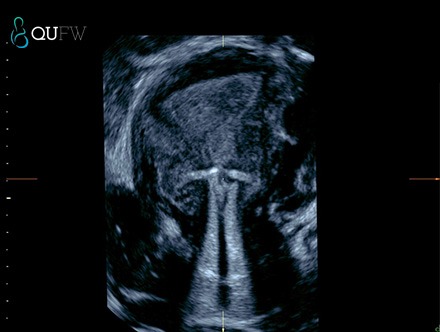

3D reconstructed image of displaced IUCD low in the endometrial cavity, with perforation of the myometrium